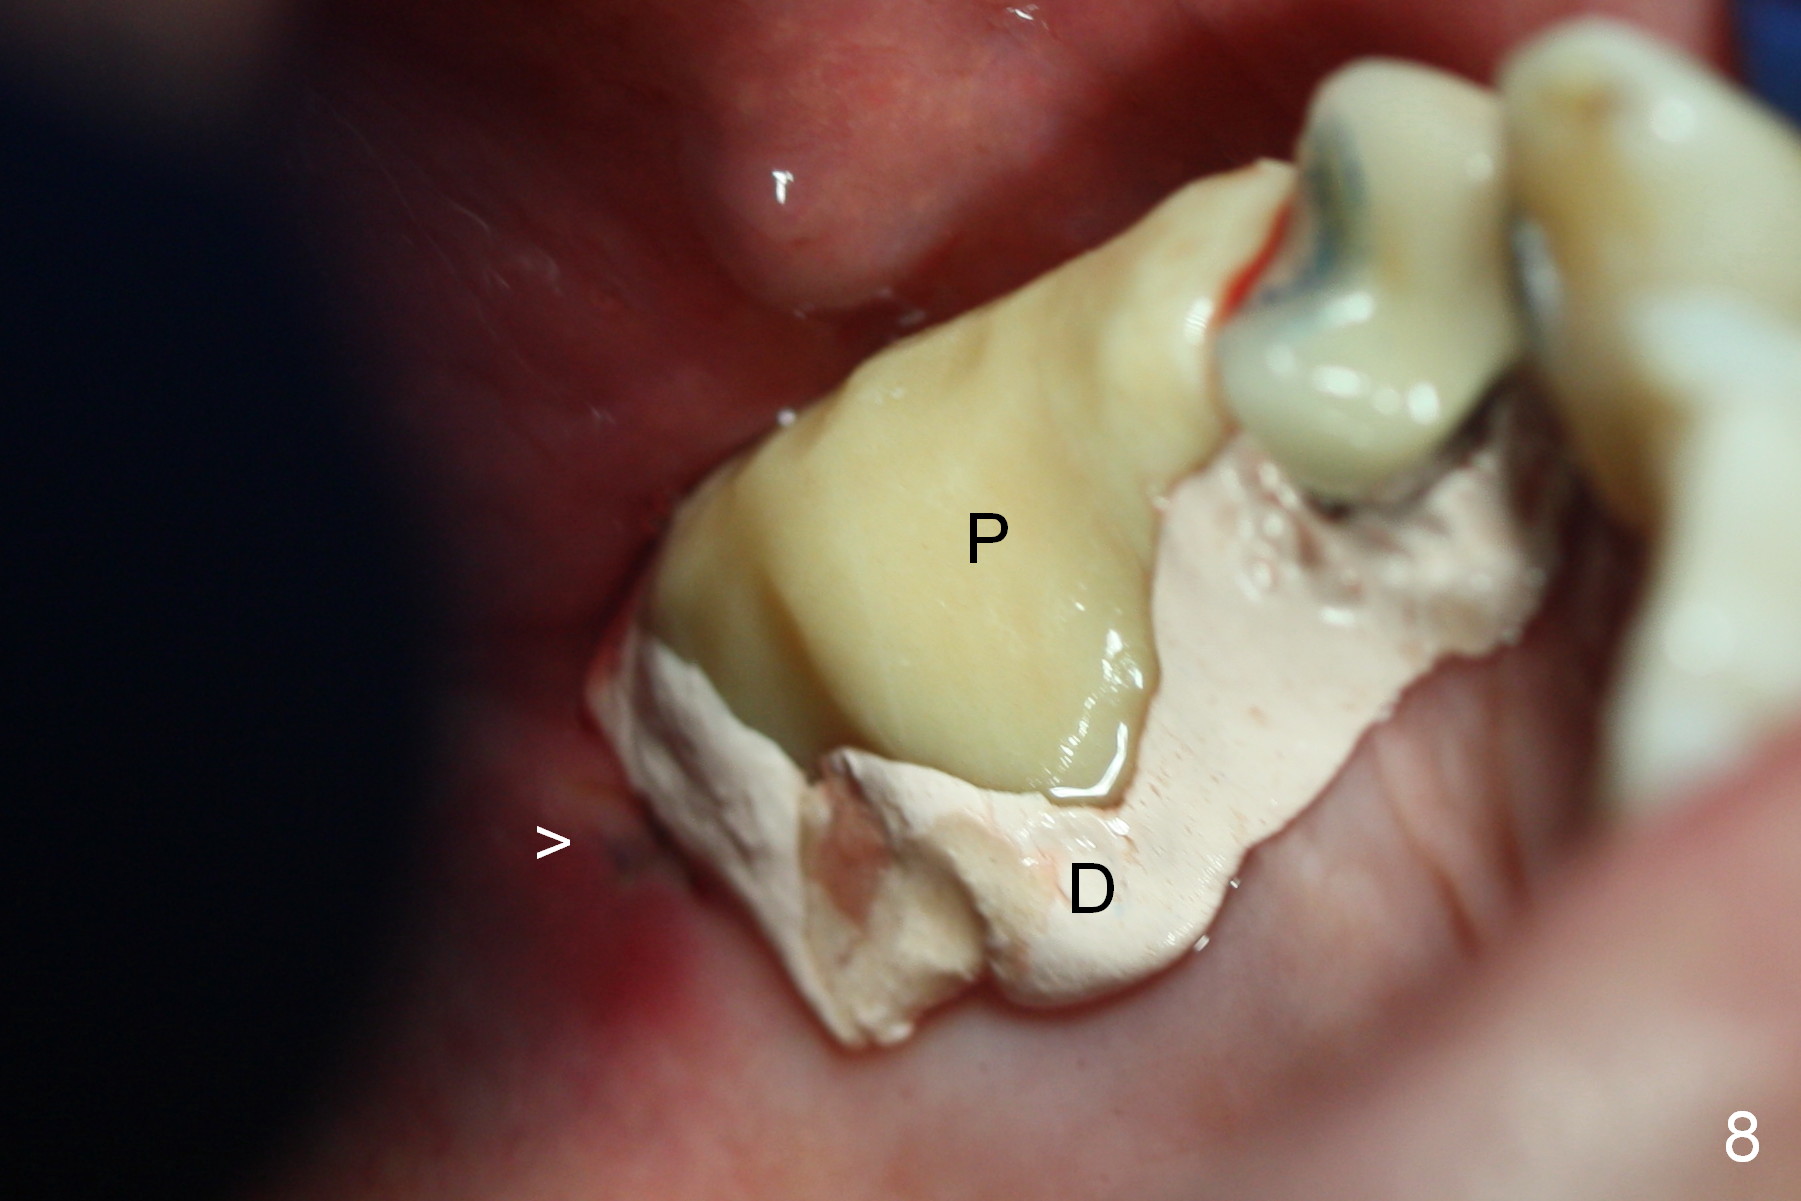

Insertion torque of the three implants is ~ 50 Ncm. Three long (because of severe vertical bone resorption (Fig.1,6)) abutments are placed immediately for immediate splinted provisional (Fig.7,8 P). The latter should have hemostatic effect. Application of peridontal dressing (D) has additional hemostatic function, exerting pressure the most anterior (Fig.7 between the teeth #5,6) and the most posterior (Fig.8 arrow) incision, where the provisional cannot. Sulcus incision is good to remove subgingival calculus. It seems that chronic periodontits and bruxism play roles in pathogenesis of bone loss.